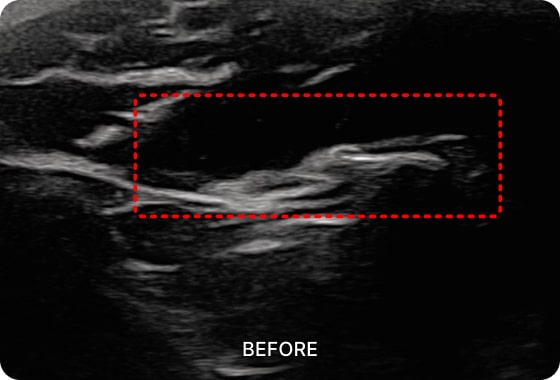

초음파 유도 시술을 통해

턱관절 장애 통증을 유발하는

심부 근육을 치료할 수 있습니다.

01. PDRN 약침

PDRN 약침은 인체의 DNA와 90% 이상 유사한 구조로 세포 증식을 활성화하여

손상된 조직을 복구하는 효과가 뛰어납니다. 초음파를 활용하여 신경을 압박하는

염증을 박리하고 손상된 조직을 재생합니다.